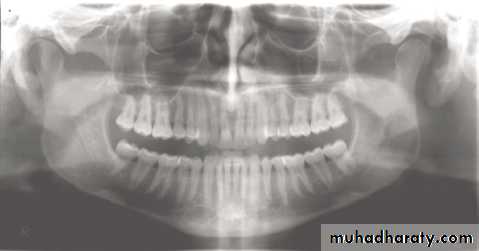

1, Mandibular condyle. 2, Articular eminence. 3, Coronoid process of mandible superimposed on zygomatic arch. 4, Posterior wall of maxillary sinus. 5, Posterior wall of zygomatic process of maxilla. 6, Hard palate. 7, Nasal septum. 8, Tip of nose. 9, Dorsum of tongue. 10, Hyoid superimposed over inferior border of mandible. 11, Inferior border of maxillary sinus. 12, Image of cervical spine. 13, Medial border of maxillary sinus. 14, Infraorbital canal. 15, Infraorbital rim. 16, Pterygomaxillary fissure. 17, Anterior border of the pterygoid plates. 18, Lateral pterygoid plate superimposed over soft palate and coronoid process of mandible. 19, Ear lobe. 20, Inferior border of mandibular canal. 21, Mental foramen. 22, Posterior wall of nasopharynx. 23, Inferior border of mandible superimposed from opposite side. 24, Soft palate over mandibular foramen of mandible.